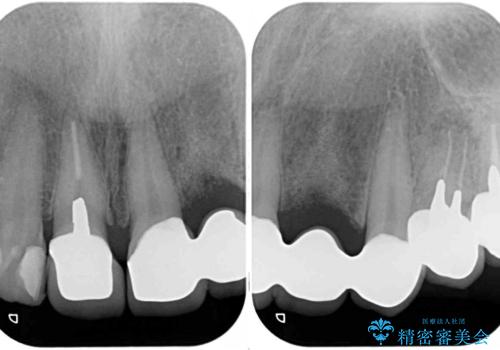

- 歯を削る量が少ないとの触れ込みで最近接着ブリッジを装着したものの、そのブリッジと歯の間に隙間ができているとのことで来院された患者様です。

歯の裏側を一層だけ削り、接着力に頼ったブリッジを装着してはみたものの、案の定咬む力に負けて、接着が剥がれてしまっていました。

歯を削る量は増えますが、より長い期間再治療なく使用していただくことを最優先に考え、フルカバレッジのオールセラミックブリッジにて補綴することとしました。

他にも、奥歯の銀歯の下にもむし歯が多くあり、痛みが生じていたため、根管治療などを行った上で、オールセラミッククラウンにて補綴治療することとしました。